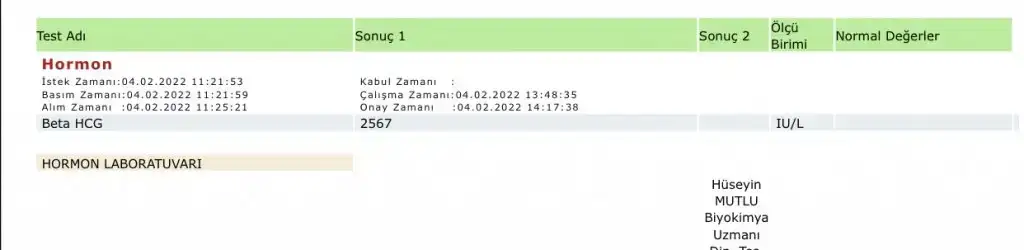

Merhaba hanımlar 1 Şubatta adet olmam gerekiyordu olmayınca akşamı test yaptım çift çizgi çıktı hemen kan verdim beta hcg 753.7 çıktı dün ( 3 şubat) bir damla kan geldi korktum bugün doktorumla görüştüm erken olduğu için ultrasonda gözükmez tekrar beta hcg ye baktır 1500 civarina geldiyse sıkıntı yok demektir dedi bende tekrar kan verdim bu sefer de değerim 2567 çıktı doktor yarın gel ultrasonda bakalım dedi şimdi merak ediyorum kısa sürede bu kadar yükselmesi normal mi yoksa ikiz gebelik olabilir mi ve kaç haftalık oluyor son adetimin ilk günü 2 Ocak bu arada ilk gebeliğim şimdiden teşekkürler

Alakası yok onla benim düşükte o degedi tek di ultrason da bile bu değer çoğul dedi tek çıktı normal bu kadar yüksek olması iki günde bir iki katı katlıyor ultrason da gözüküyor üsten bu değerle git bak buraya da yazMerhaba hanımlar 1 Şubatta adet olmam gerekiyordu olmayınca akşamı test yaptım çift çizgi çıktı hemen kan verdim beta hcg 753.7 çıktı dün ( 3 şubat) bir damla kan geldi korktum bugün doktorumla görüştüm erken olduğu için ultrasonda gözükmez tekrar beta hcg ye baktır 1500 civarina geldiyse sıkıntı yok demektir dedi bende tekrar kan verdim bu sefer de değerim 2567 çıktı doktor yarın gel ultrasonda bakalım dedi şimdi merak ediyorum kısa sürede bu kadar yükselmesi normal mi yoksa ikiz gebelik olabilir mi ve kaç haftalık oluyor son adetimin ilk günü 2 Ocak bu arada ilk gebeliğim şimdiden teşekkürler

Bugün gittim doktora rahim tersmiş ama bir sorun yokmuş tek keseymiş ve tam istediği gelişimdeymiş gayet sağlıklı dedi düşük önleyici ve kan ilacı verdi beta hcg değeri ile eş değermiş gelişimiAlakası yok onla benim düşükte o degedi tek di ultrason da bile bu değer çoğul dedi tek çıktı normal bu kadar yüksek olması iki günde bir iki katı katlıyor ultrason da gözüküyor üsten bu değerle git bak buraya da yaz

Ablamın daha yüksekti tek gebelik di beeta ya gire bilmez kimse usg de belli olur yarine zaten değer yükselir 3000 olur ordan gözükür beta 30 60 90 diye gdiip te ikiz olan da okudum ben 20 25 30 diye gidipte olan da ikiz gördüm beta ile alakası yok beta isterse 800.00 bin olsun tek de olabilir hakkınızda hayırlısı olsun inşallahMerhaba hanımlar 1 Şubatta adet olmam gerekiyordu olmayınca akşamı test yaptım çift çizgi çıktı hemen kan verdim beta hcg 753.7 çıktı dün ( 3 şubat) bir damla kan geldi korktum bugün doktorumla görüştüm erken olduğu için ultrasonda gözükmez tekrar beta hcg ye baktır 1500 civarina geldiyse sıkıntı yok demektir dedi bende tekrar kan verdim bu sefer de değerim 2567 çıktı doktor yarın gel ultrasonda bakalım dedi şimdi merak ediyorum kısa sürede bu kadar yükselmesi normal mi yoksa ikiz gebelik olabilir mi ve kaç haftalık oluyor son adetimin ilk günü 2 Ocak bu arada ilk gebeliğim şimdiden teşekkürler